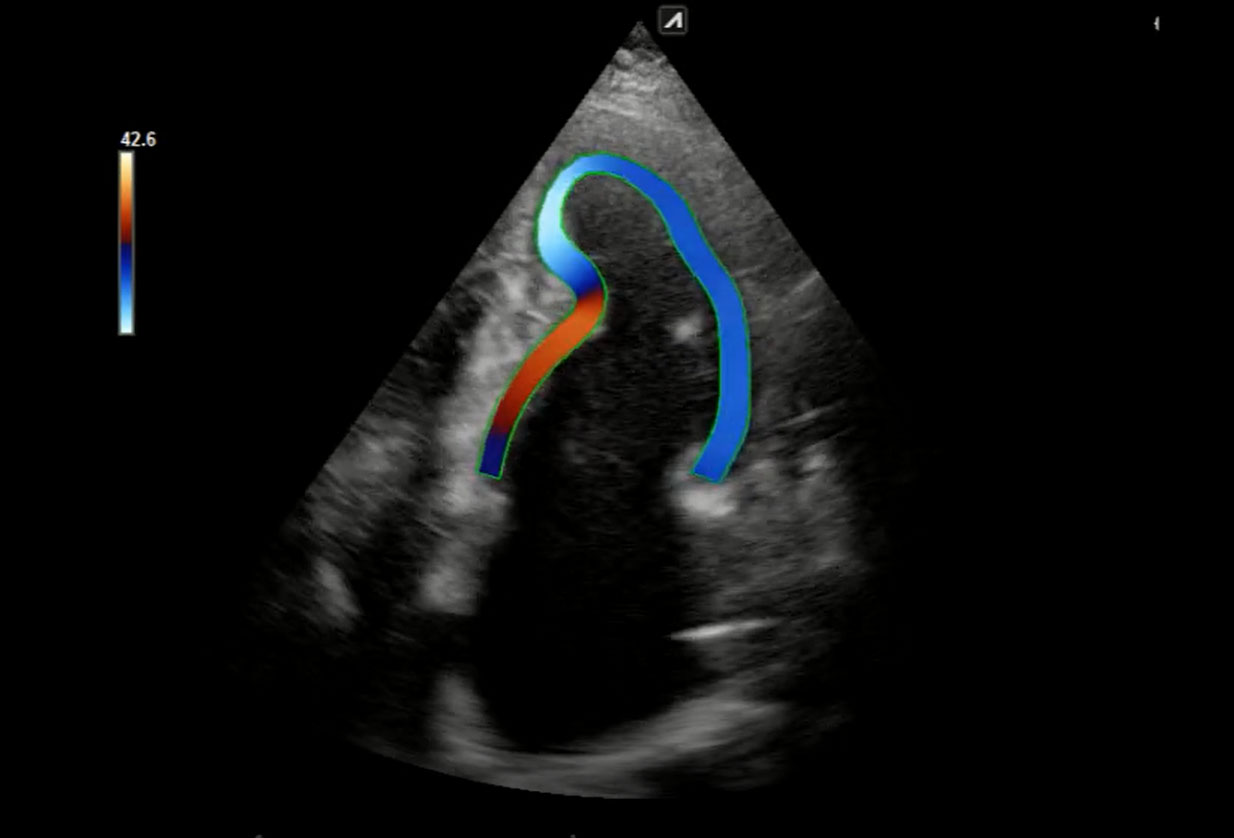

Μελέτη ιστικής παραμόρφωσης (myocardial strain)

Στο ιατρείο μας έχουμε τη δυνατόητα εφαρμογής νεότερης τεχνολογίας υπερηχογραφικών τεχνικών (longitudinal strain) που αυξάνουν κατά πολύ την διαγνωστική αποτελεσματικότητα. Το λογισμικό αναλύει την λειτουργία της καρδιάς και εντοπίζει τμηματική και συνολική δυσλειτουργία που δεν ειναι εμφανής στο γυμνό μάτι.

Εξειδικευμένη εξέταση μελέτης ιστικής παραμόρφωσης

H εξέταση γίνεται με εφαρμογή νεότερης τεχνολογίας υπερηχογραφικών τεχνικών (longitudinal strain) που αυξάνουν κατά πολύ την διαγνωστική αποτελεσματικότητα.